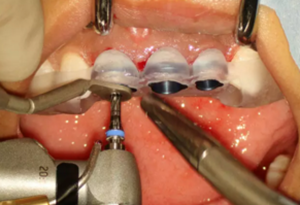

(2)即刻種植、即刻臨時修復(fù)。術(shù)中不翻瓣微創(chuàng)拔除牙根,牙槽 窩骨壁完整。在多級導(dǎo)板輔助下完成種植窩洞制備,植入Bego柱形種植 體,型號分別為:上頜右側(cè)中切牙位點4.1mm×15mm、上頜左側(cè)中切牙 位點?3.75mm×15mm、上頜左側(cè)側(cè)切牙位點3.25mm×15mm,扭矩均為 35N·cm。種植體與唇側(cè)骨壁間隙約2mm,植入Bio-Oss®Collagen骨膠 原。戴入橋用鈦臨時基臺,臨時冠就位順利,自凝樹脂口內(nèi)粘接后適當(dāng)修整 外形,充分磨光,調(diào) 至正中 、前伸 和側(cè)方 與對頜牙均無接觸。術(shù)后 根尖片顯示種植體位置、方向良好。

圖8 導(dǎo)板輔助下備洞

圖9 植入種植體

圖10 植入骨膠原

圖11 戴入臨時修復(fù)體